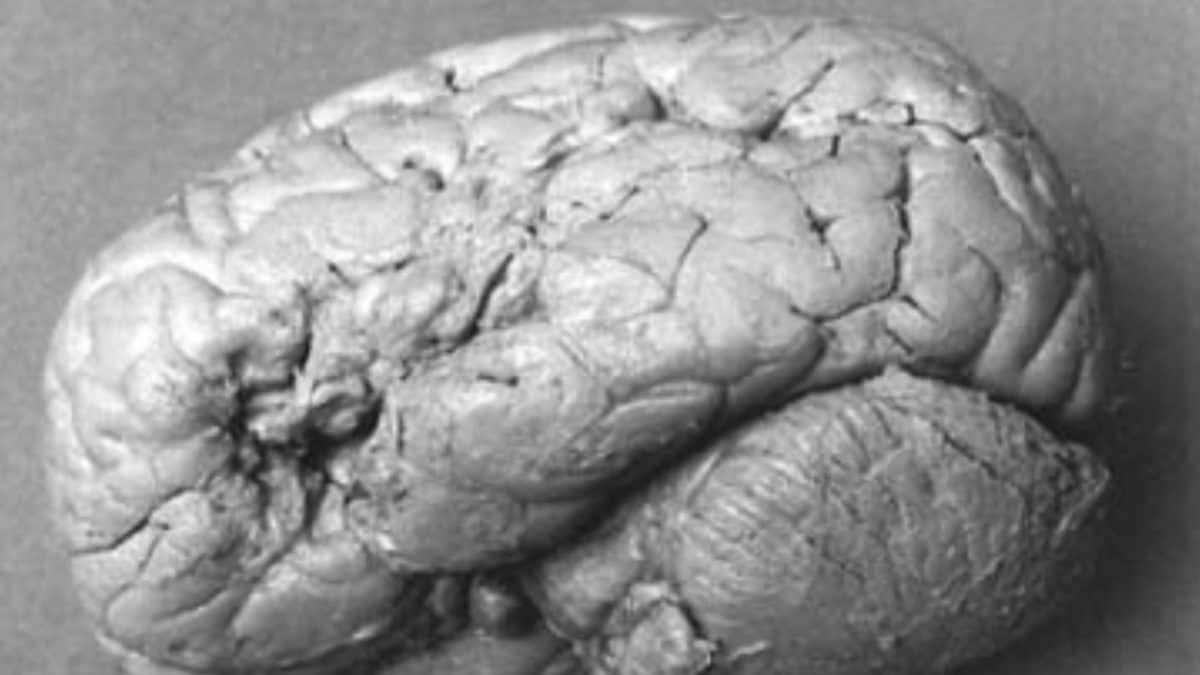

Il suo cervello fu esaminato dopo la sua morte dal medico e anatomista Paul Broca, che scoprì infatti lesioni evidenti e localizzate nell’area frontale, precisamente nella seconda e terza circonvoluzione dell’emisfero sinistro. Questo portò Broca a formulare l’ipotesi che quell’area sia la sede neurale dei meccanismi che rendono possibile il linguaggio parlato.

Qui incontra il dottor Broca, che decide poi di effettuare approfondimenti per via autoptica e di studiare attentamente il cervello di Leborgne: decide poi anche di donarlo poi al Museo anatomico Dupuytren, istituto scientifico oggi chiuso e il cui materiale è stata trasferito al Campus Jussieu insieme ad altre collezioni della facoltà di medicina della Sorbona.

L’osservazione del cervello del paziente “tan tan” porta Broca a proseguire i suoi approfondimenti e osservare altri cervelli di pazienti deceduti e affetti dallo stesso disturbo, e dà così il via ai fondamentali studi che permettono di dichiarare la correlazione tra lesioni di quella specifica area del cervello e l'incapacità di parlare.

In realtà, la pubblicazione dello studio di Broca porta la comunità scientifica a prendere posizioni controverse, tra cui quella del neurologo Pierre Marie, allora attivo nell’ospedale della Salpêtrière, che non era d’accordo sulla posizione esatta della lesione, punto di vista che viene ripreso anche da uno studio pubblicato nel 2000, che vede l’afasia di Leborgne come “globale”, quindi più estesa, e non relativa solo a quella specifica area.

In alcuni studi successivi si è ipotizzato anche che le lesioni nel cervello di Leborgne fossero provocate da cisti dovute alla sifilide, ma in realtà – così evidenzia lo storico Domanski – negli studi di Broca non si trova traccia di questo. Il cervello del paziente “tan tan” è stato oggetto di studi anche in tempi recenti, tra cui scansioni di maggior precisione effettuate negli anni 80, da cui è emerso che la lesione era ancora più profonda di quanto evidenziato dal dottor Broca. Ulteriori approfondimenti possono essere fatti facendo riferimenti ai numerosi studi sull’argomento.